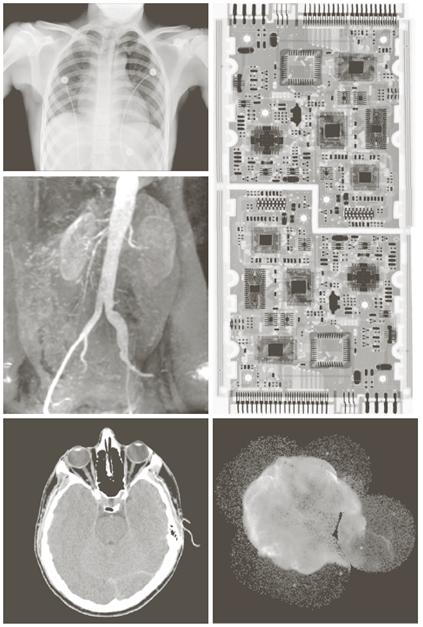

X-ray image

Visual band and infrared image

a) 항암제 Taxol b) 콜레스테롤 c) 마이크로프로세서

Visual band image – 영상처리에 의한 품질검사

a) 회로 기판

b) 포장 알약

- 주요 응용분야: 의학(MRI: magnetic resonance image), 천문학

인체의 MRI 무릎, 척추

Other imaging modalities

a)아기1 b)아기2 c)갑상선 d)손상된근육